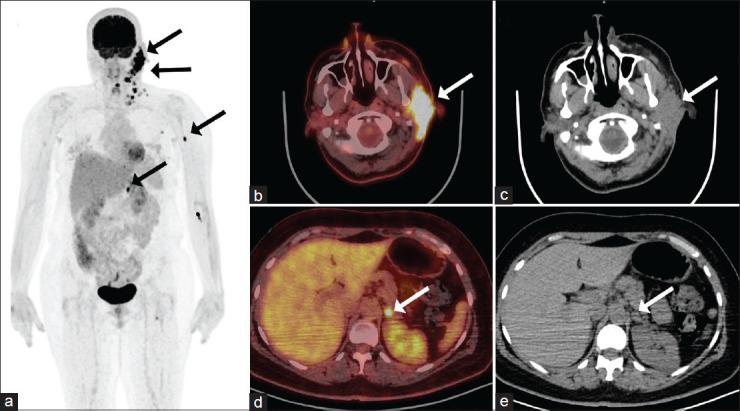

Conventional imaging techniques, while essential, occasionally fall short in identifying elusive metastatic lesions, leading to delayed diagnoses and compromised patient outcomes. Gallium-68 fibroblast activating protein inhibitor (Ga-FAPI) positron emission tomography/computed tomography (PET/CT), leveraging the distinct affinity of fibroblast activation protein for cancer-associated fibroblasts, emerges as a promising solution to bridge this diagnostic gap. Parotid gland adenocarcinoma is a relatively rare malignancy with metastasis typically occurring in regional lymph nodes and distant sites such as the lungs and bones. However, there have been limited reported cases of rare metastatic sites such as the adrenal gland. This exceptional case report details the clinical presentation, diagnostic workup, and management steps of a rare case of a 47-year-old female patient diagnosed with parotid gland adenocarcinoma with confusing metastasis to the ipsilateral adrenal gland which was confirmed later with a follow-up Ga-FAPI PET/CT scan. We aim to highlight FAPI unique ability to illuminate metastatic foci in challenging anatomical locations.

传统成像技术虽然至关重要,但在识别难以捉摸的转移病灶时偶尔会有所不足,导致诊断延迟和患者预后受损。镓-68成纤维细胞激活蛋白抑制剂(Ga-FAPI)正电子发射断层扫描/计算机断层扫描(PET/CT)利用成纤维细胞激活蛋白对癌症相关成纤维细胞的独特亲和力,成为弥合这一诊断差距的有前景的解决方案。腮腺腺癌是一种相对罕见的恶性肿瘤,转移通常发生在区域淋巴结以及肺部和骨骼等远处部位。然而,肾上腺等罕见转移部位的报道病例有限。本特殊病例报告详细介绍了一名47岁女性患者的临床表现、诊断检查和管理步骤,该患者被诊断为腮腺腺癌,伴有同侧肾上腺令人困惑的转移,随后通过Ga-FAPI PET/CT随访扫描得以证实。我们旨在突出FAPI在照亮具有挑战性的解剖位置的转移灶方面的独特能力。